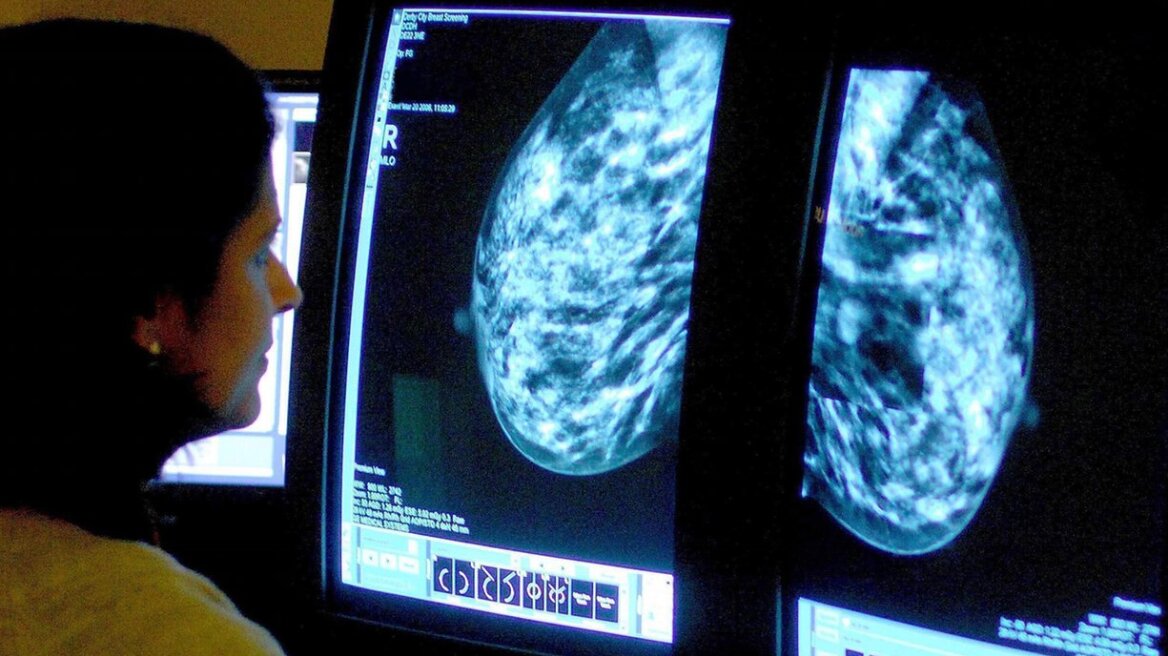

O συνδυασμός του φαρμάκου Herceptin με άλλο, πριν την διαδικασία της επέμβασης συρρικνώνει, ακόμα και διαλύει εντελώς καρκινικούς όγκους στο στήθος, ακόμα και αν ο καρκίνος είναι επιθετικής μορφής, και μάλιστα σε χρόνο μικρότερο των δύο εβδομάδων. Αυτό έδειξαν τα «εκπληκτικά», όπως χαρακτηρίστηκαν, αποτελέσματα μελέτης βρετανών επιστημόνων, που παρουσιάστηκαν στο 10ο Ευρωπαϊκό Συνέδριο για τον καρκίνο του στήθους, στο Άμστερνταμ. Εφόσον μάλιστα τα ευρήματα της μελέτης εφαρμοστούν σωστά, θα μπορούσαν να οδηγήσουν σε λιγότερες χημειοθεραπείες.

Περίπου το ένα τέταρτο από τις 66 γυναίκες με καρκίνο του στήθους της μορφής HER2 έλαβαν επί 11 ημέρες έναν συνδυασμό τραστουζουμάμπης (που είναι η γενετική ονομασία για το Herceptin) και λαπατινίμπης και είδαν τους όγκους στα στήθη τους να συρικνώνονται δραστικά ή ακόμα και να εξαφανίζονται.